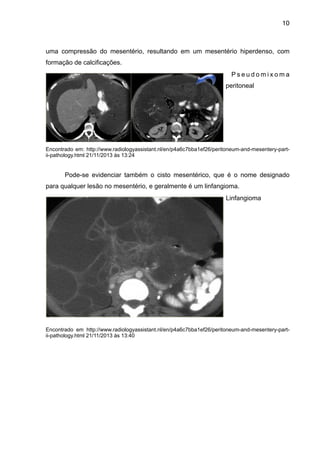

Com isso pode-se exibir algumas imagens relacionadas com patologias

associadas ao mesentério, como uma caso de pseudomixoma peritoneal, em que há

10

uma compressão do mesentério, resultando em um mesentério hiperdenso, com

formação de calcificações.

Pode-se evidenciar também o cisto mesentérico, que é o nome designado

para qualquer lesão no mesentério, e geralmente é um linfangioma.